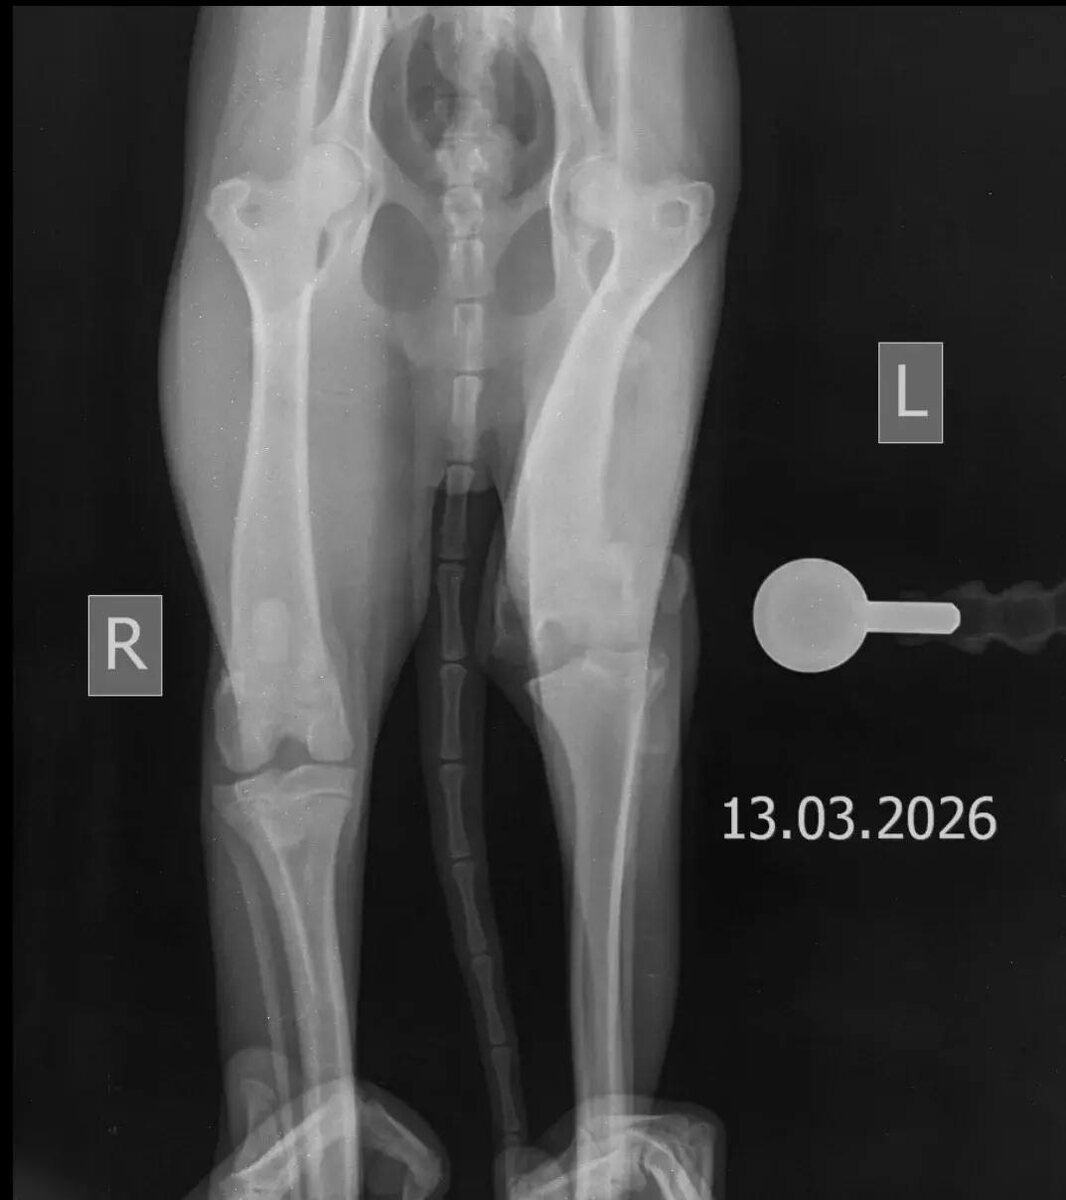

Привет, дорогой Волшебник! Меня зовут Персик. У меня очень болит лапка и нужна операция🥺 Помогите мне, пожалуйста, жить без боли и бегать на четырёх лапах 😭

❗️Сумма к сбору 77.450 рублей🙏